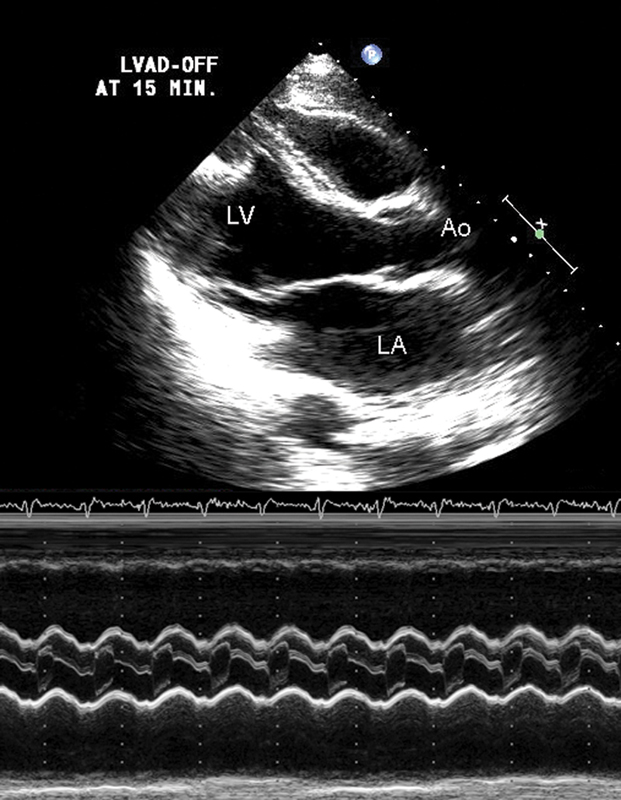

فحوصات تشخيصية لبعض امراض القلب والشرايين التاجية